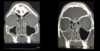

DESCRIBE LA TAC

- corte coronal - imagen de ocupación en el seno maxilar derecho (estimado: más o menos un 90%), se ve más o menos homogénea - imagen de ocupación parcial de superficie convexa y lisa (estimado: 40%) (puede ser un mucocele o un quiste de retención y px sinsusitico crónico) seno maxilar izq - se observa desviación leve hacia la izq del septum